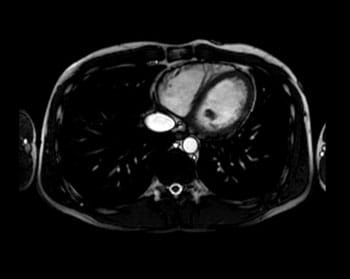

心臓MRIについて

当院では、心臓MRI検査を年間81件程度行っています。心臓MRIでは心臓の壁運動や心筋梗塞部位、心筋虚血、冠動脈形態の評価を行うことができます。また平成30年4月より、心筋組織の性状評価を行うことができるようになり、より精度の高い診断ができるようになりました。

冠動脈の状態を造影剤を用いることなく描出することが可能です。また造影剤を用いた心臓MRI検査は、CT検査などでしか得られなかった情報を一度に取得できます。

心臓は常に動いているので少しずつしか撮影することができず検査時間が長くなります。検査時間は30~60分程度です。